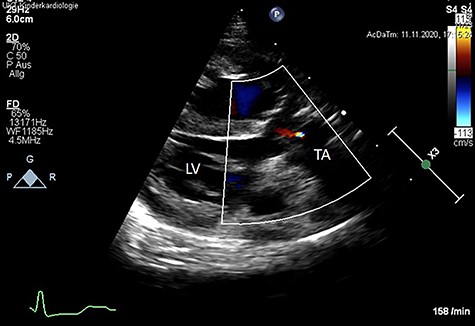

We present a case of a female patient referred at 10 days of age with 22q11.2 deletion syndrome, TAC type A2 of the van Praagh classification with a regurgitant, quadricuspid TV and VSD (Fig. 1). The patient had signs of heart failure and respiratory insufficiency and had to be intubated and transferred to the pediatric intensive care unit pre-operatively. After hemodynamic stabilization, surgery was performed.

Color Doppler echocardiography in the parasternal long axis view shows severe TV regurgitation. RV: right ventricle, LV: left ventricle, TA: truncus arteriosus.